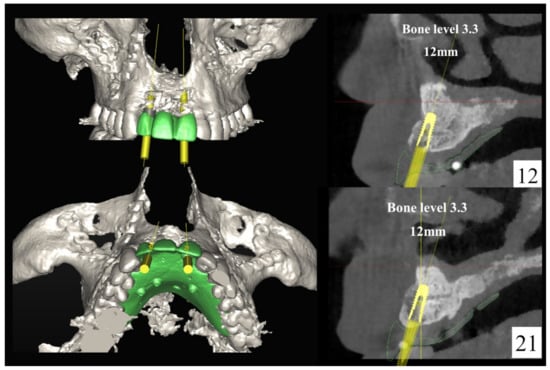

The number, the length, the diameter and the placement of computational virtual implants were determined with respect to the design of the final prosthesis the available residual bone volume and the anatomical limitations according to the previously described technical procedure (Figure 16, Figure 17, Figure 18, Figure 19, Figure 20 and Figure 21).

Figure 18.

Three-dimensional (3D) planning of the number, the diameter and the axis of dental implants with respect to the design of the final virtual maxillary prosthesis.

Figure 19.

6.2.4. Intra-Operative Documentation:

In March 2013, twelve guided dental implants were placed at sites # 12, # 13, # 15, # 22, # 23, # 25, # 33, # 34, # 36, # 43, # 44, and # 46 (Figure 22, Figure 23, Figure 24, Figure 25 and Figure 26)